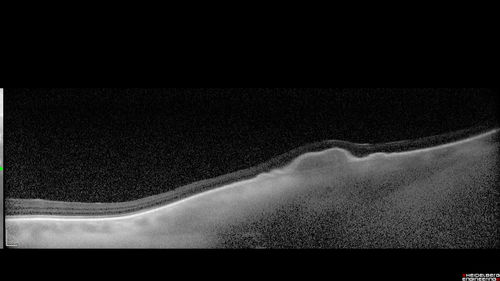

Choroidal Nevus with Drusen

82 year old female with flat nevus for 3 years.